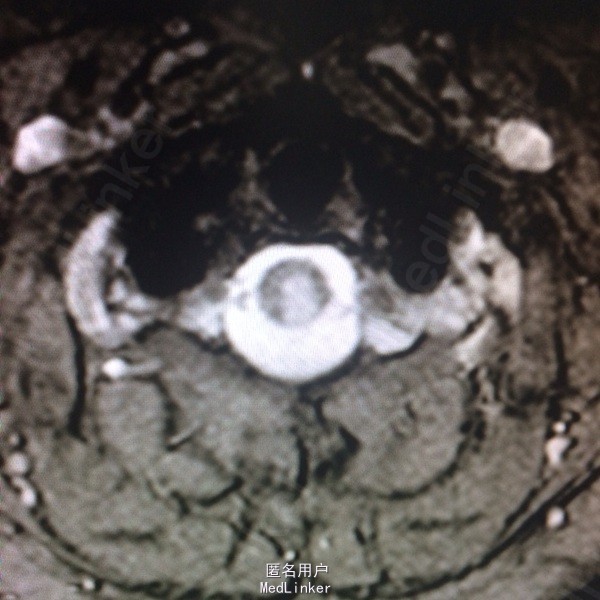

查体:左侧上肢、左侧颈项部、左侧躯干浅感觉减退,左上肢有力5-级,左侧肢体腱反射(+),余(-)。 辅助检查:头颅CT:右侧顶叶、左侧岛叶少许腔隙性梗塞,侧脑室旁脑白质变性,脑萎缩。 入院后查风湿三项:RF:74IU/ml,肌酣:92umol/L。尿酸:362umol/L,胆固醇:6.44mmol/L。糖耐量试验正常。输血四项正常。血沉、自免八项、血管炎3项、血找狼疮细胞均正常。心脏彩超正常。椎动脉彩超、颈动脉彩超正常。肌电图:左侧正中神经腕部节段性损害(感觉纤维受累,脱髓鞘改变),符合左侧腕管综合征电生理改变;左侧正中神经、左侧尺神经F波异常,提示近端神经根(C8-T1)受累,请结合临床。头颅MR:双侧额叶皮层下多发小缺血变性灶,未见急性梗死;右侧椎动脉颅内段较左侧明显细小,颅脑MRA未见异常;右侧桥小脑角增宽,未除蛛网膜囊肿。颈椎MR:颈椎轻度后弓,退行性变:C2/3、C3/4、C4/5、C5/6椎间盘突出(后正中型);C6/7椎间盘膨出,C1椎体水平脊髓内异常信号影,建议增强扫描。增强扫描示:C1水平脊髓内异常信号,脊髓炎与多发性硬化相鉴别。

诊断:急性脊髓炎。 治疗经过:入院后予B1、甲钴胺营养神经,患者症状稍有好转,在完善颈椎MR后考虑急性脊髓炎,予激素冲击治疗。